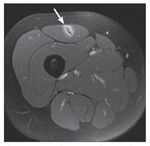

Quadriceps muscle strains frequently occur in sports that require repetitive kicking and sprinting. An axial MRI view of a rectus femoris central tendon injury shows fluid enhancement around the central tendon, the acute bull’s-eye lesion (arrow).